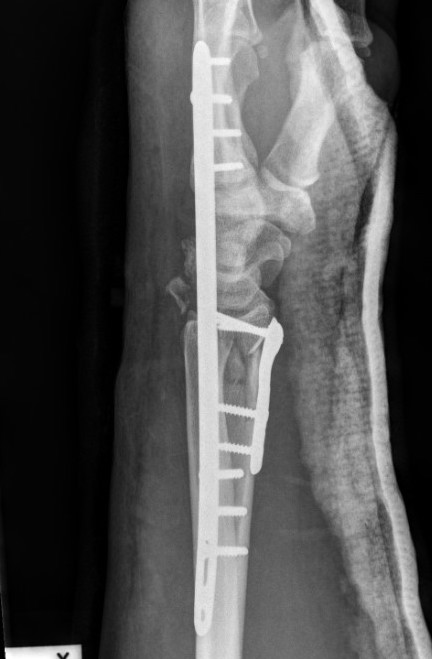

Dorsal distraction plating

Indication

Internal radiocarpal distraction

- unreconstructable distal radius fractures

- early weight bearing in poly trauma patients

- osteoporotic bone

Advantage - no pin site infection from external fixation

Disadvantage - need to remove plate at 3 - 4 months once fracture united

Technique

AO surgery foundation extended dorsal approach wrist

AO surgery foundation dorsal distraction plate

Arthrex dorsal spanning plate 2 incision video

Extended dorsal approach

- protect sensory radial nerve

- open 3rd extensor compartment / retract EPL radially

- mobilized 4th extensor compartment / retract EDC ulnarly

- bare area of radius proximally between EDC and ECRB / ECRL

Fixation to 2nd or 3rd metacarpal first

- 2nd metacarpal: under 2nd extensor compartment

- 3rd metacarpal: under 4th extensor compartment

- reduce / distract joint

- +/- additional radius fixation

Results

- systematic review of dorsal distraction plating

- 50% of wrist flexion extension compared to contralateral limb

- grip strength 80%